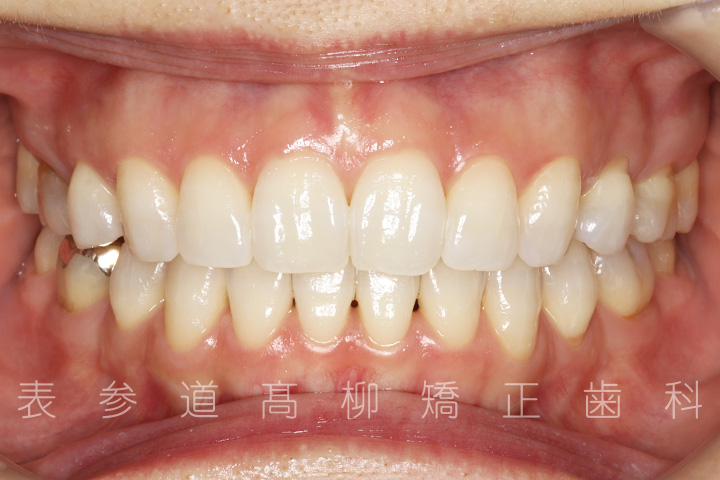

口呼吸と舌癖で前歯が咬み合わない患者様の症例をご紹介いたします。

治療前→治療後

術前術後の比較